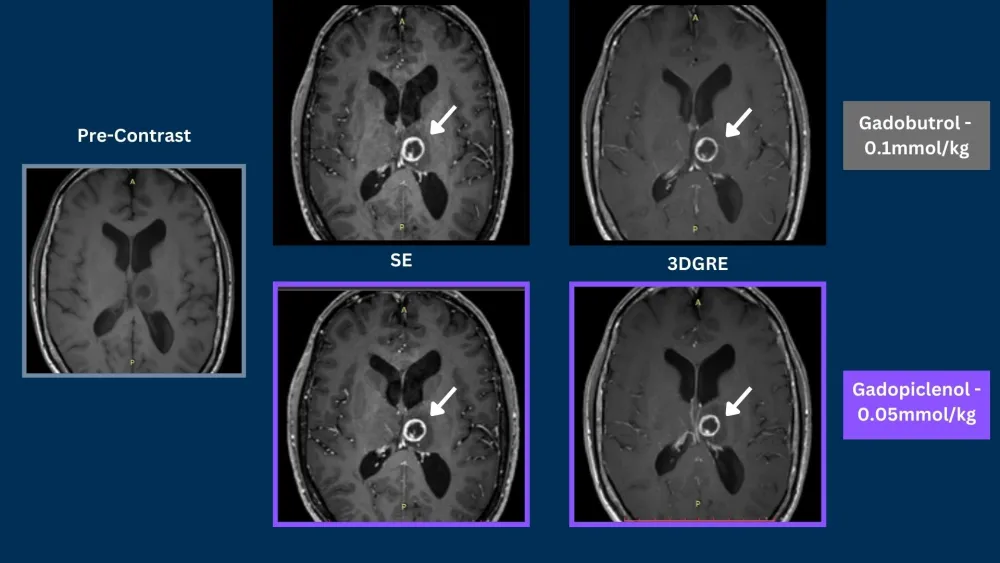

Phase III clinical trials, in CNS and Body, demonstrated that gadopiclenol at a dose of 0.05 mmol/kg was noninferior to gadobutrol at a dose of 0.1 mmol/kg in terms of lesion visualization.5,6

Case 454 year old male1

Brain Metastases

SE = Spin Echo, GRE = Gradient Echo, 3DGRE = 3D Gradient Echo, TSE = Turbo Spin Echo

Phase III PICTURE trial in CNS demonstrated that gadopiclenol at a dose of 0.05 mmol/kg was noninferior to gadobutrol at a dose of 0.1 mmol/kg in terms of lesion visualization.5